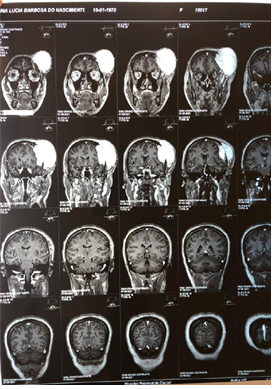

Figure 4A Contrast-enhanced magnetic resonance image showing a tumor in the extraaxial region of left frontal involvement in sagittal section.

Figure 4B Contrast-enhanced magnetic resonance imaging showing a tumor in the extraaxial region of left frontal involvement in coronal section.